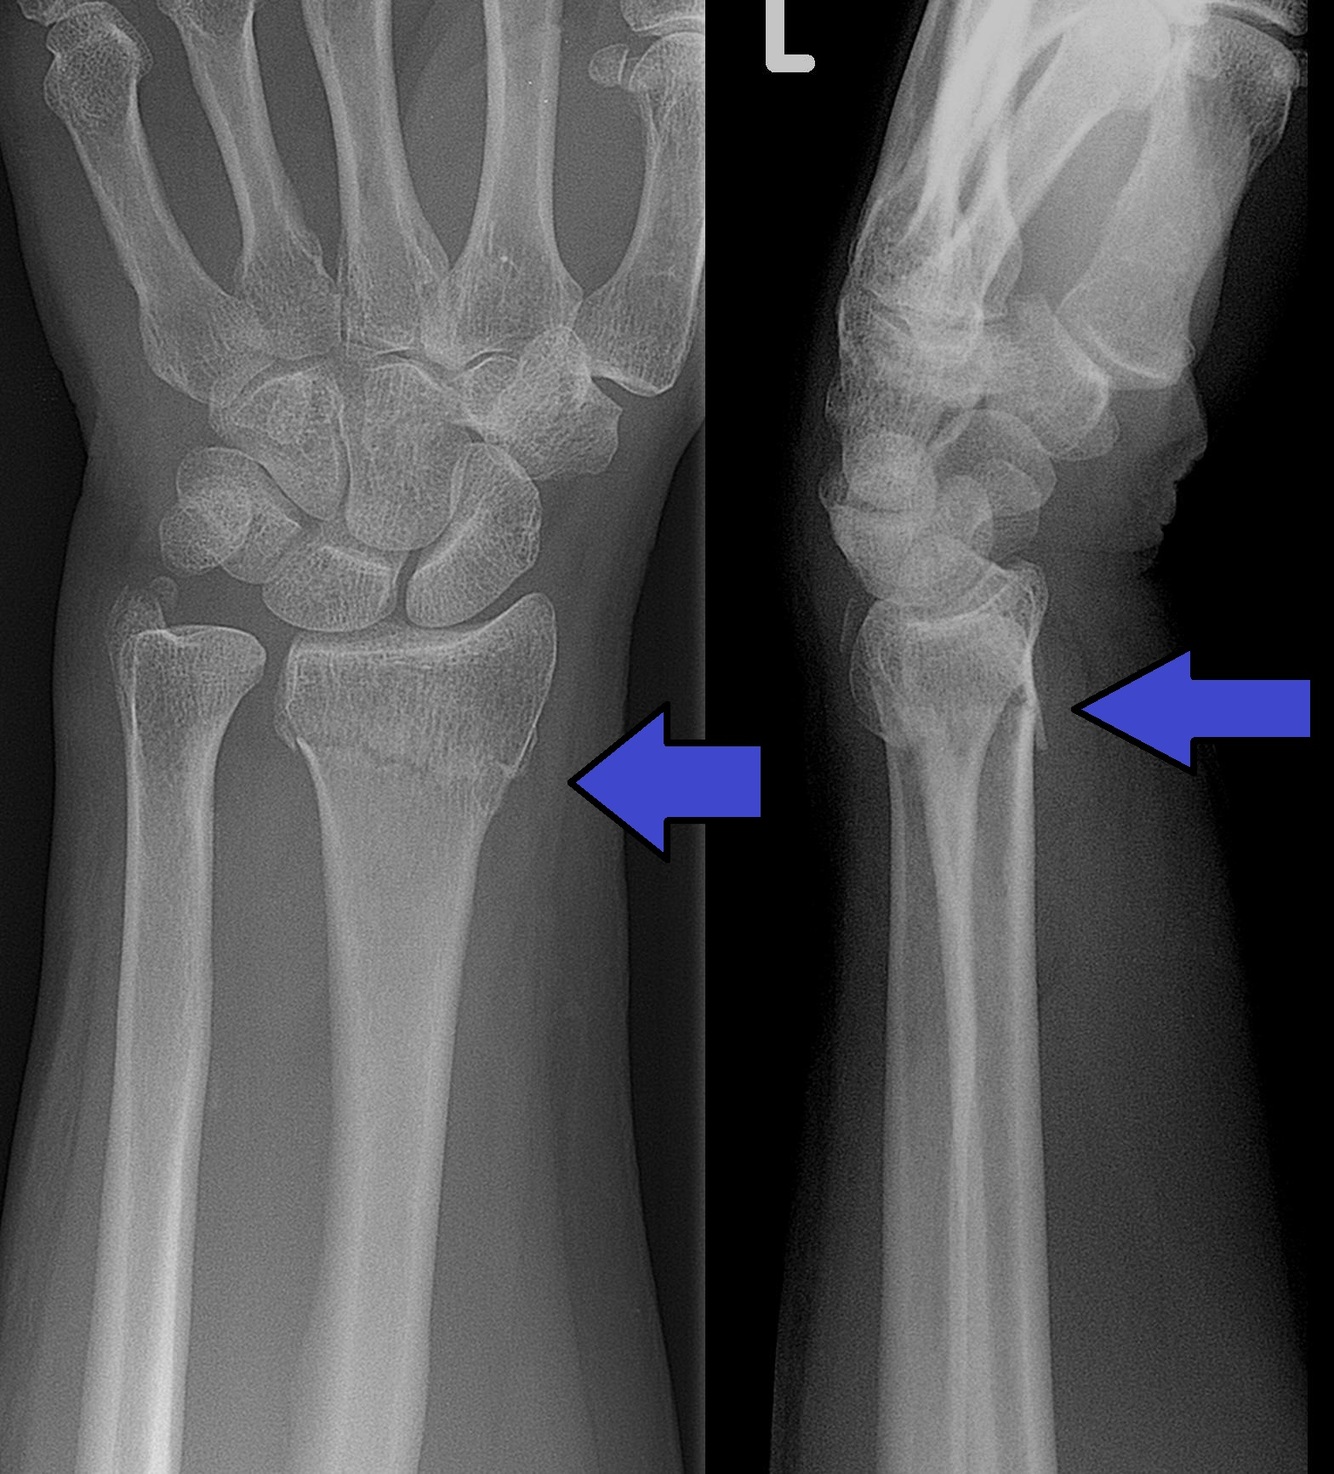

(4) Types of distal radius fractures (just name)

Colle’s

Management: reduction of fracture under regional anaesthesia + plaster backslab for 6 weeks + X ray

Complications: Carpal tunnel syndrome, mal-union, stiffness, rupture of extensor pollicis longus